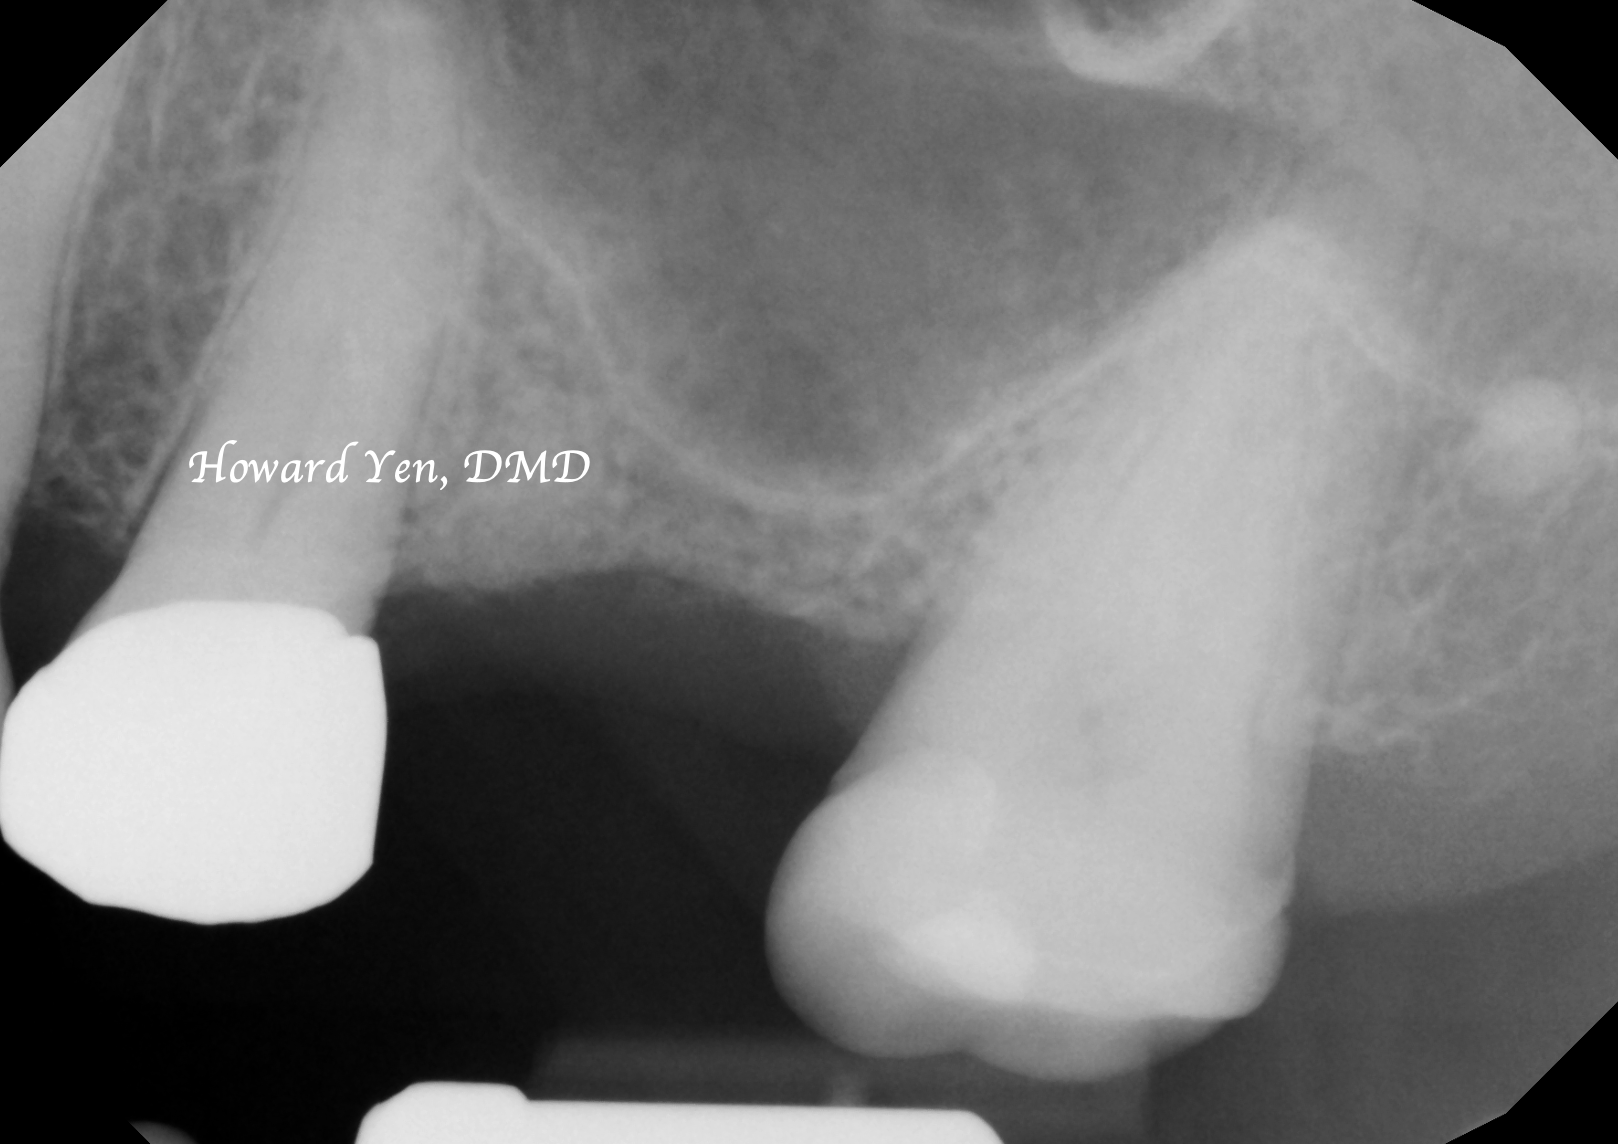

There’s the presence of maxillary sinus cavities around our nasal area and upper jaw bone. When an upper back tooth (molar or premolar) is removed, the sinus air cavity will quickly replace the jaw bone space once held by the roots of the molar/premolar. Some surgical interventions can be completed to help reduce the shrinkage of the bone volume or to help reconstruct/re-build the lost jaw bone volume around the sinus region to facilitate the placement of dental implants.